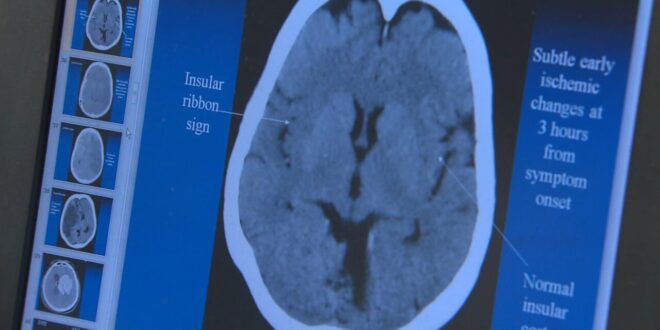

التصلّب المتعدّد مرض مناعي ذاتي مزمن، غالباً ما يُسبب إعاقة، ويؤثّر على الجهاز العصبي المركزي. ونظراً لأنّ غالبية المصابين بهذا المرض، والبالغ عددهم مليون أمريكي تقريباً، هنّ من النساء، فقد يعاني العديد منهنّ من أعراض مضاعفة. تشرح ماندي غايثر كيف يمكن أن تتشابه أعراض انقطاع الطمث وأعراض التصلب المتعدّد.